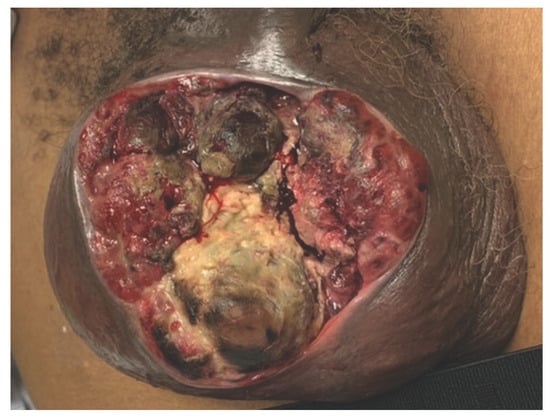

Pure Yolk Sac Tumor of the Testis with Scrotal Invasion in an Adult Male